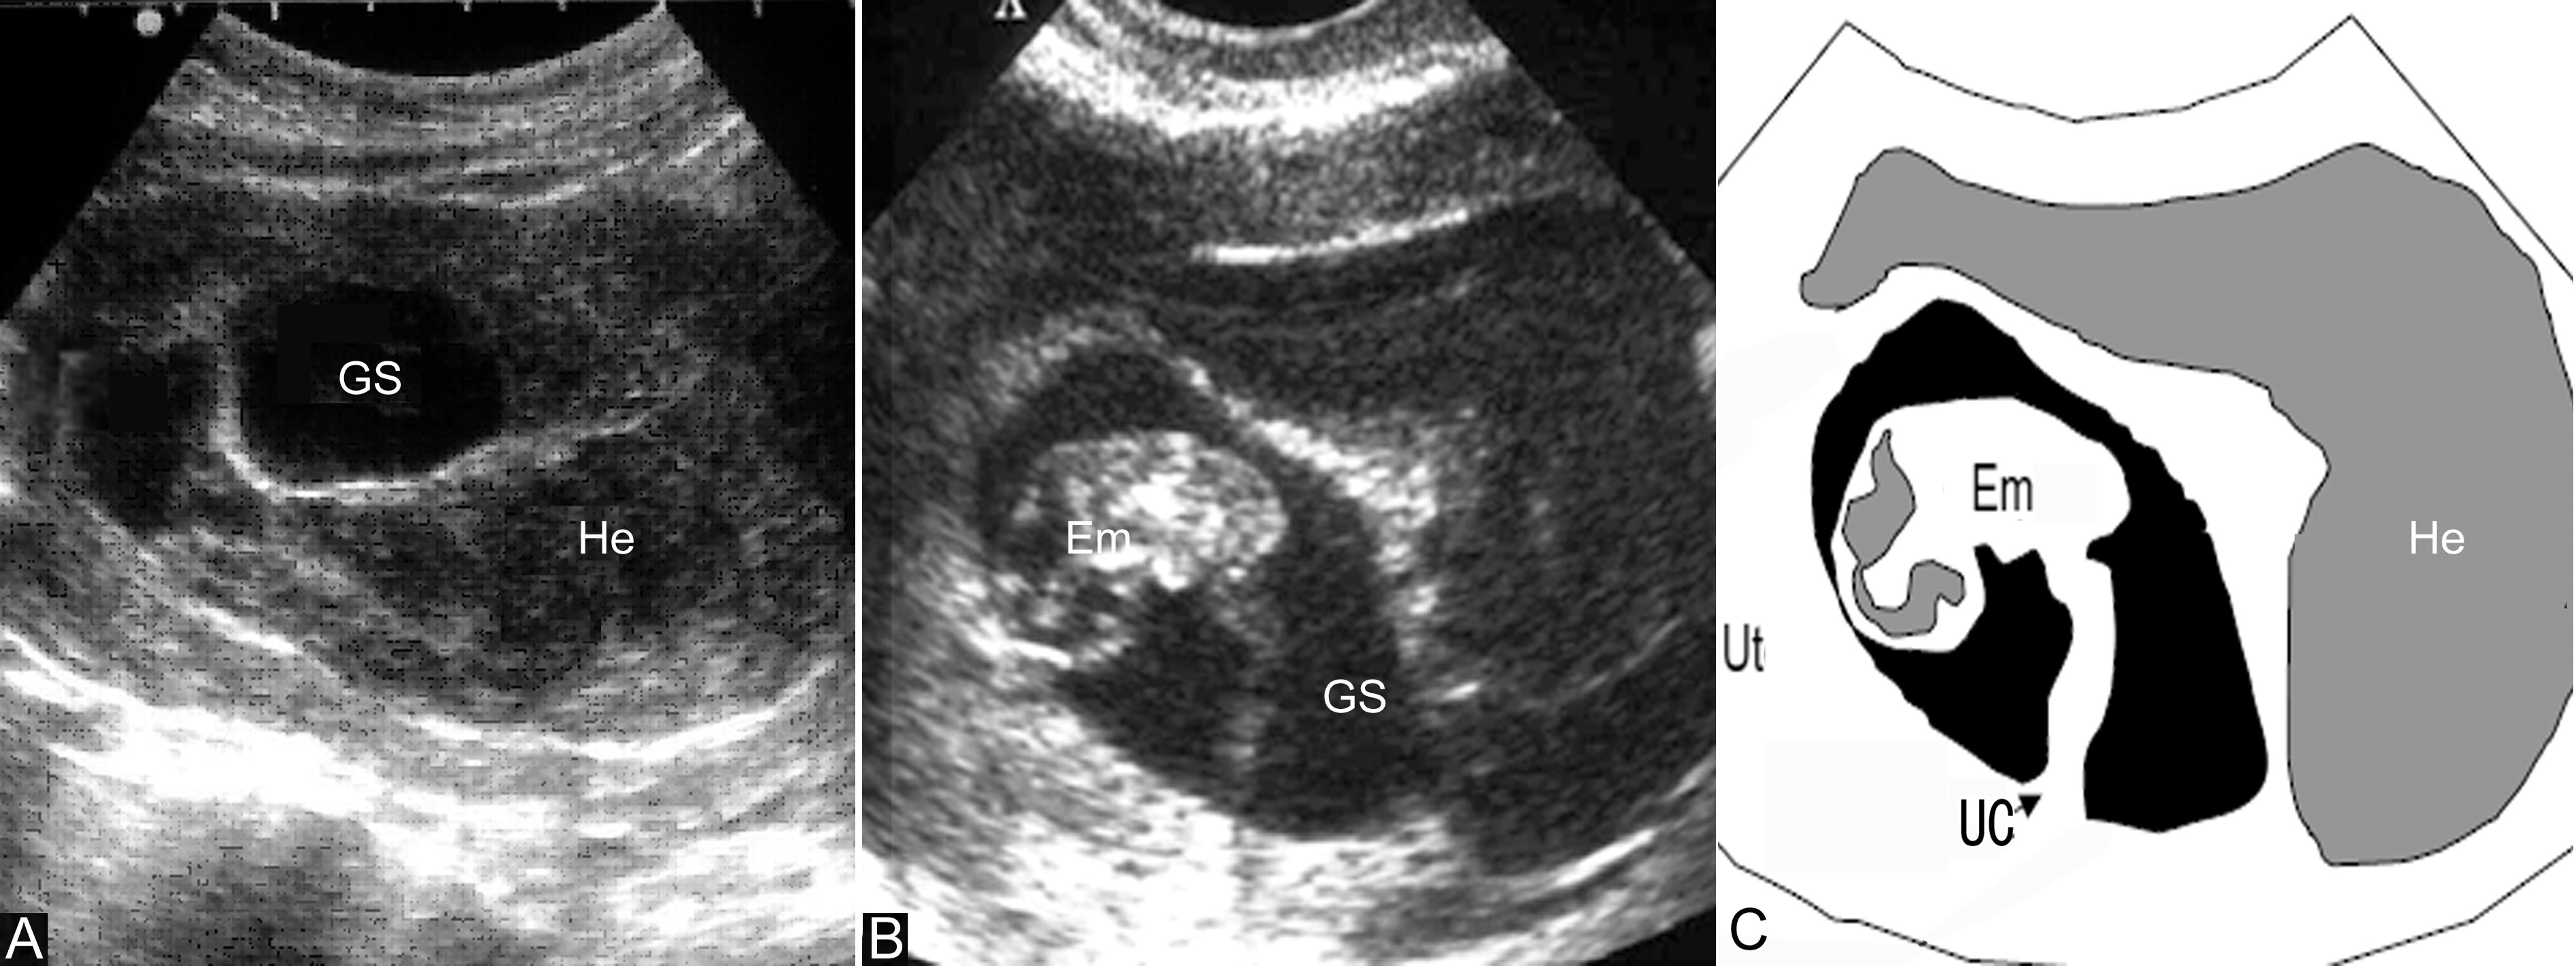

子宫和妊娠囊大小与停经月份相符,回声规则,形态及位置无明显异常变化,妊娠囊内部仍可见存活的胚胎或胎儿,大小与妊娠月份一致。妊娠囊一侧或下方可显示低回声或无回声区,提示有绒毛膜下血肿存在(图1,2),但多数较小,胎盘附着处回声正常;部分声像图可完全无异常发现。

图1绒毛膜下血肿声像图:孕囊(Gs)后方及下方可见不均匀的血块(Ha)回声;C:示意图

图2绒毛膜下血肿声像图:孕囊(GC)下方可见血肿